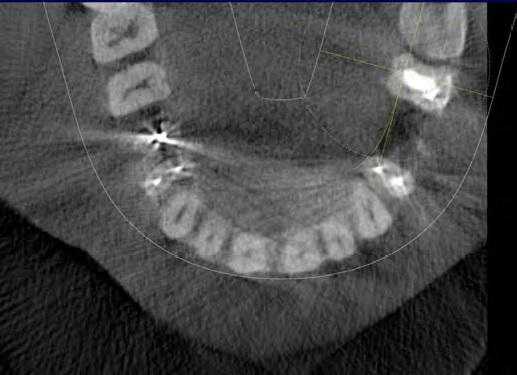

В периапикальной области обоих корней определялся обширный сливной очаг деструкции кости протяженностью 11х6 мм, который распространялся до кортикальной выстилки нижней челюсти канала с ее локальным разрушением (рис. 6) .

Рис. 6. КЛКТ, МПР. Прицельная визуализация апикальных очагов деструкции в обл. 4.7 зуба.

После уточнения анатомо-топографических особенностей системы корневого канала было проведено дальнейшее повторное эндодонтическое лечение зуба 4.7 с инструментальной обработкой 5 каналов, ирригацией 3%-ным раствором гипохлорита натрия, временным пломбированием каналов гидроокисью кальция ( Calasept ) на 2 надели. Каналы запломбированы гуттаперчей с эпоксидным силлером, коронковая часть восстановлена постоянной реставрацией.

Параллельно с этим на КТ была выявлена несостоятельность реставрации 4.6 зуба. Пациентке было рекомендовано провести его лечение. Однако она обратилась в клинику только через полгода с острой болью в области 4.6 зуба. После клинического обследования и анализа особенностей строения канально-корневой системы 4.6 зуба на КЛКТ (рис. 7) было проведено эндодонтическое лечение 5-канального нижнего правого первого моляра по поводу необратимого симптоматического периодонтита 4.6 зуба.